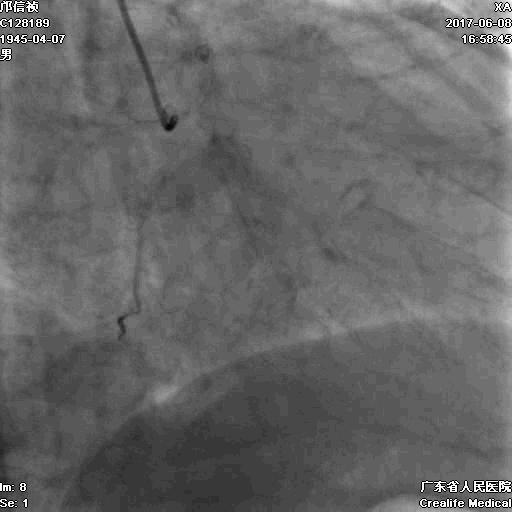

首先:IVUS指导下干预LAD

4.0mm*13mm药物支架